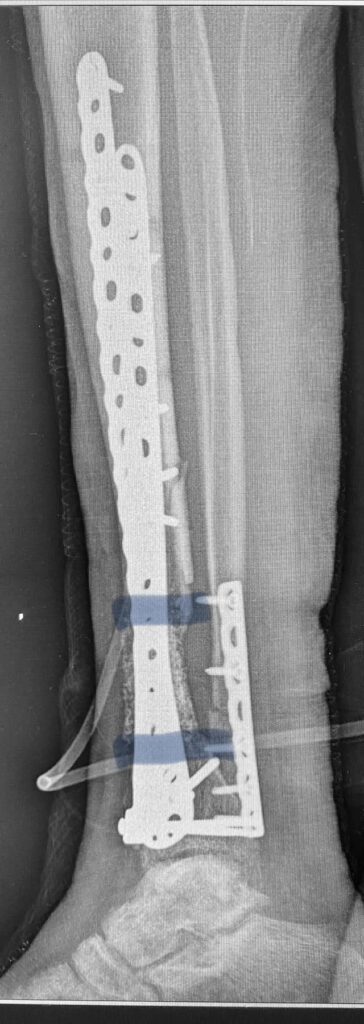

На первом фото – это заменитель кости, на втором (черно-белом, дабы Фейсбук не волновался) поверх собственной кости пациента насыпаны гранулы заменителя кости. Они блескучие такие. Недаром этот заменитель кости называют ещё и «биостекло». Потом – рентгенограмма после заключительной операции.

Тут вы видите рентгенограммы двух пациентов. В одном случае ранение голени у коленного сустава. В другом случае у сустава голеностопного с переломом костей. Поэтому там пластина еще стоит.

Эти двое пациентов, чьи рентгенограммы вы видите, были прооперированы Председателем нашей Ассоциации AO Trauma Ukraine Олександром Рихтером в одном из военных госпиталей на западе Украины. Все зажило отлично.

Для первого раненого хватило 10 кубических сантиметров Bonalive, на второго – там, где пластина, ушло 20 «кубиков». Итого, в дополнение ко всему прочему – это 1500 евро.